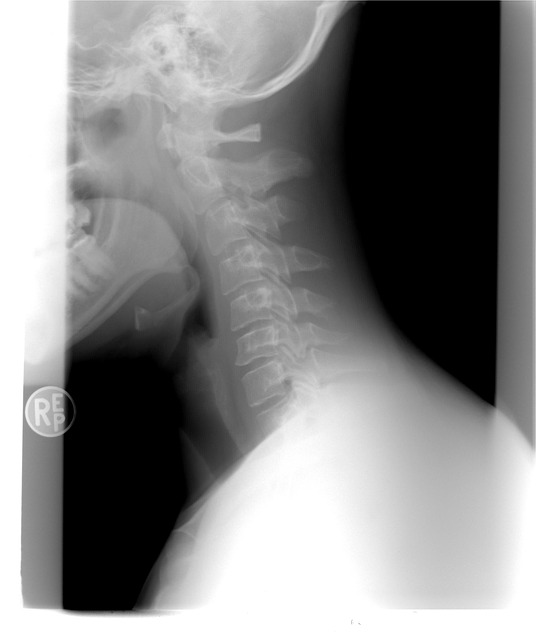

갑상선 목부음은 갑상선종으로 불리우는데요. 이게 크기가 커지거나 통증이 심해지면 숨을 쉬거나 음식을 삼키는데 불편함이 생겨 일상생활속에서 많은 불편함을 느낄 수 있다고 해요.

갑상선종은 종류가 많아서 구분하여 치료를 하게 되는데요. 다결절 갑상선종은 가장 흔한 형태로서 여러개의 결절이 갑상선에 발견되는것을 말합니다. 미만성 갑상선종은 갑상선이 전체적으로 붓는것을 말합니다. 흉골 하 갑상선종은 갑상선이 흉골 뒤쪽에서 자라나는 걸로 기도나 주변 혈관을 압박하게 되고 계속 크기가 자랄 경우에는 수술이 필요합니다.

갑상선 제거 수술을 진행해야 할수도 있는데요. 갑상선의 크기가 커져 이물감이 심하게 느껴지거나 일상생활에 영향을 주는경우나 이로 인하여 호흡곤란이 생기는 경우에는 수술로 제거 해야합니다. 갑상선 제거 수술은 전체 제거나 부분제거로 진행하게 되는데요. 갑상선 제거 수술을 하는 경우에는 갑상선 호르몬을 별도로 복용하여야 합니다.